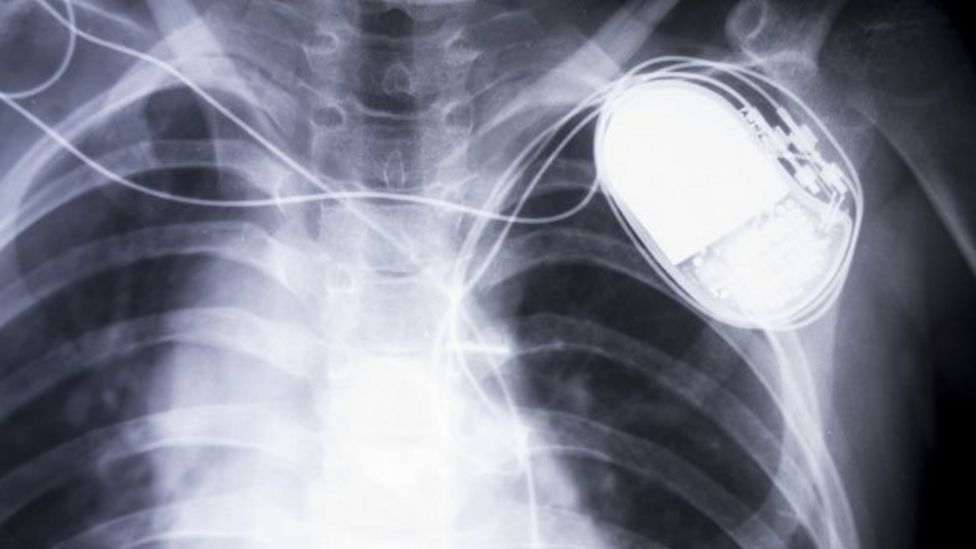

pacemaker Rare Earth Magnets And Pacemakers Magnets may interfere with the operation of pacemakers and implantable cardioverter defibrillators (icds), according to a. Such strengths were once rare from household items, and only found near devices like stereo speakers and cordless tools. The purpose of this study is to determine the separation distance between consumer electronic devices that may create. Their observational study with the specific concern. Rare Earth Magnets And Pacemakers.